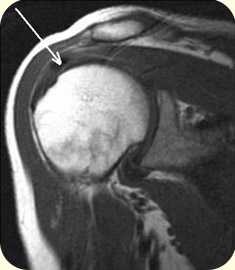

Также в постановке диагноза помогает МРТ исследование.

на МРТ участки кальцификатов отображаются, как отдельные фокусы (очаги) ослабления сигнала